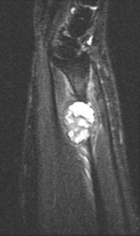

32 y/o spanish speaking female with one month of intermittent pain associated with a mass in left wrist. Pain began after playing the drums. No constitutional sx.

PE: Palpable 2cm mass dorsal distal forearm, TTP w/o crep, no LAN, erythema, edema, neurovascularly intact